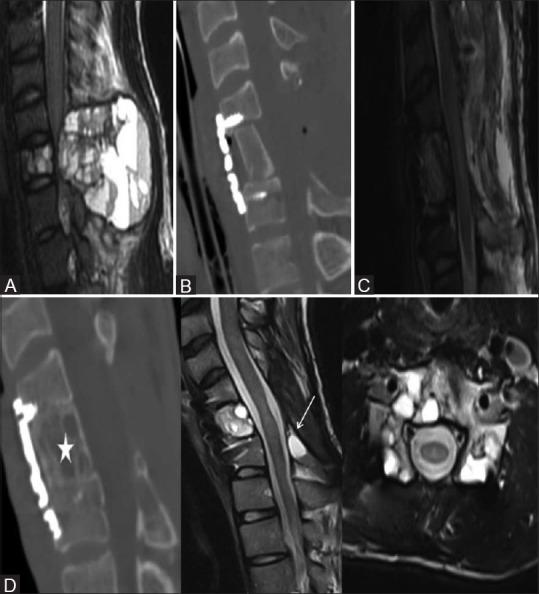

多节段颈椎椎体次全切除术后使用长支撑植骨特有的并发症:先进成像技术的应用

Complications exclusive to long strut grafts used following multilevel cervical corpectomy: Utilization of advanced imaging techniques.

When surgical decompression of cervical spine is considered, multilevel cervical corpectomy with long strut grafts is the preferred treatment. This procedure is used in a variety of pathologies including degenerative disease, tumors, trauma and infection. Corpectomy with interbody grafting helps in adequate spinal canal and neural decompression compared to multilevel discectomy, which could be difficult as well as inadequate. Fibular/iliac strut grafts are used for reconstruction along with a stabilizing hardware in this procedure. So far, complete imaging spectrum of complications exclusive to strut graft has not been reported in the literature. This pictorial essay presents complications exclusive to the strut graft, utility of advanced imaging in diagnosis and a brief note on the clinical management of complications.

摘要

当考虑进行颈椎手术减压时,多节段颈椎椎体次全切除并使用长支撑植骨是首选的治疗方法。该手术适用于多种病理情况,包括退行性疾病、肿瘤、创伤和感染。与多节段椎间盘切除术相比,椎体次全切除并椎间植骨有助于充分减压椎管和神经,因为多节段椎间盘切除术可能既困难又不充分。在此手术中,使用腓骨/髂骨支撑植骨并结合稳定的内固定器械进行重建。到目前为止,文献中尚未报道过支撑植骨特有的完整并发症影像学谱。这篇影像文章介绍了支撑植骨特有的并发症、先进影像学在诊断中的作用以及并发症临床处理的简要说明。